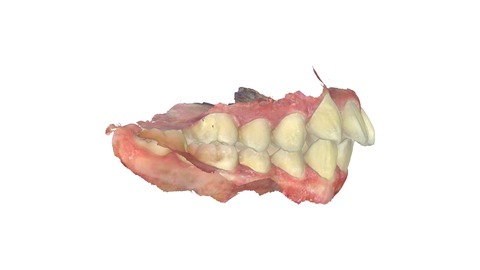

上の歯。前歯に内側に引っ込んだ歯がある。